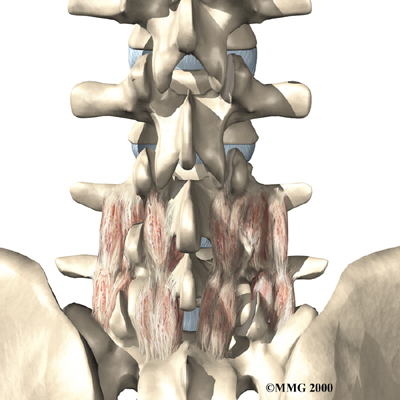

The next part of our program will include a series of strengthening exercises for the abdominal and low back muscles. Working these core muscles helps our patients begin moving easier and lessens the chances of future pain and problems. Aerobic exercises such as walking or swimming are used for easing pain and improving endurance.

The human spine is formed by 24 spinal bones, called vertebrae. Vertebrae are stacked on top of one another to form the spinal column. The spinal column gives the body its form. It is the body's main upright support. The section of the spine in the lower back is known as the lumbar spine.

The lumbar spine is made up of the lower five vertebrae. Doctors often refer to these vertebrae as L1 to L5. These five vertebrae line up to give the low back a slight inward curve. The lowest vertebra of the lumbar spine, L5, connects to the top of the sacrum, a triangular bone at the base of the spine that fits between the two pelvic bones. Some people have an extra, or sixth, lumbar vertebra. This condition doesn't usually cause any particular problems.